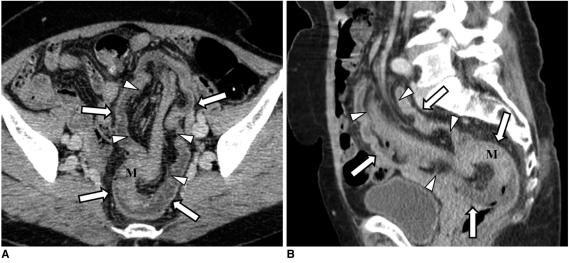

结肠癌相关结肠并发症的 CT 表现

CT findings of colonic complications associated with colon cancer.

A broad spectrum of colonic complications can occur in patients with colon cancer. Clinically, some of these complications can obscure the presence of underlying malignancies in the colon and these complications may require emergency surgical management. The complications of the colon that can be associated with colon cancer include obstruction, perforation, abscess formation, acute appendicitis, ischemic colitis and intussusception. Although the majority of these complications only rarely occur, familiarity with the various manifestations of colon cancer complications will facilitate making an accurate diagnosis and administering prompt management in these situations. The purpose of this pictorial essay is to review the CT appearance of the colonic complications associated with colon cancer.

结直肠癌患者可能会出现广泛的结肠并发症。临床上,这些并发症中的一些可能会掩盖结肠中潜在的恶性肿瘤,这些并发症可能需要紧急手术治疗。可能与结直肠癌相关的结肠并发症包括梗阻、穿孔、脓肿形成、急性阑尾炎、缺血性结肠炎和肠套叠。虽然这些并发症大多数很少见,但熟悉结直肠癌并发症的各种表现形式将有助于在这些情况下做出准确的诊断并进行及时的治疗。本文旨在通过 CT 影像回顾结直肠癌相关结肠并发症的表现。